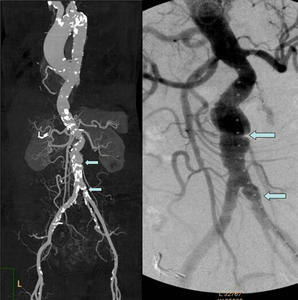

图左:术前CTA提示腹主动脉及髂动脉夹层。

图右:术中造影明确腹主动脉及髂动脉夹层。